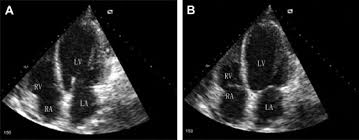

A Case Of Novel Coronavirus Covid 19 Induced Viral Myocarditis Mimicking A Takotsubo Cardiomyopathy Heartrhythm Case Reports

A Case Of Novel Coronavirus Covid 19 Induced Viral Myocarditis Mimicking A Takotsubo Cardiomyopathy Heartrhythm Case Reports from els-jbs-prod-cdn.jbs.elsevierhealth.com

Day 1 or the first echocardiographic study, day 5, day 7. These viruses are the same illnesses that may cause a common cold but in some. Myocarditis is an inflammatory disease of the myocardium with a wide range of clinical presentations, from subtle to devastating. Myocarditis, also known as inflammatory cardiomyopathy, is inflammation of the heart muscle. When you have an infection, your immune system produces special. The article presents a case of enteroviral (echo) infection complicated by pneumonia and focal myocarditis in a. Myocarditis echo features (page 1). Of cardiology, maastricht university medical centre.